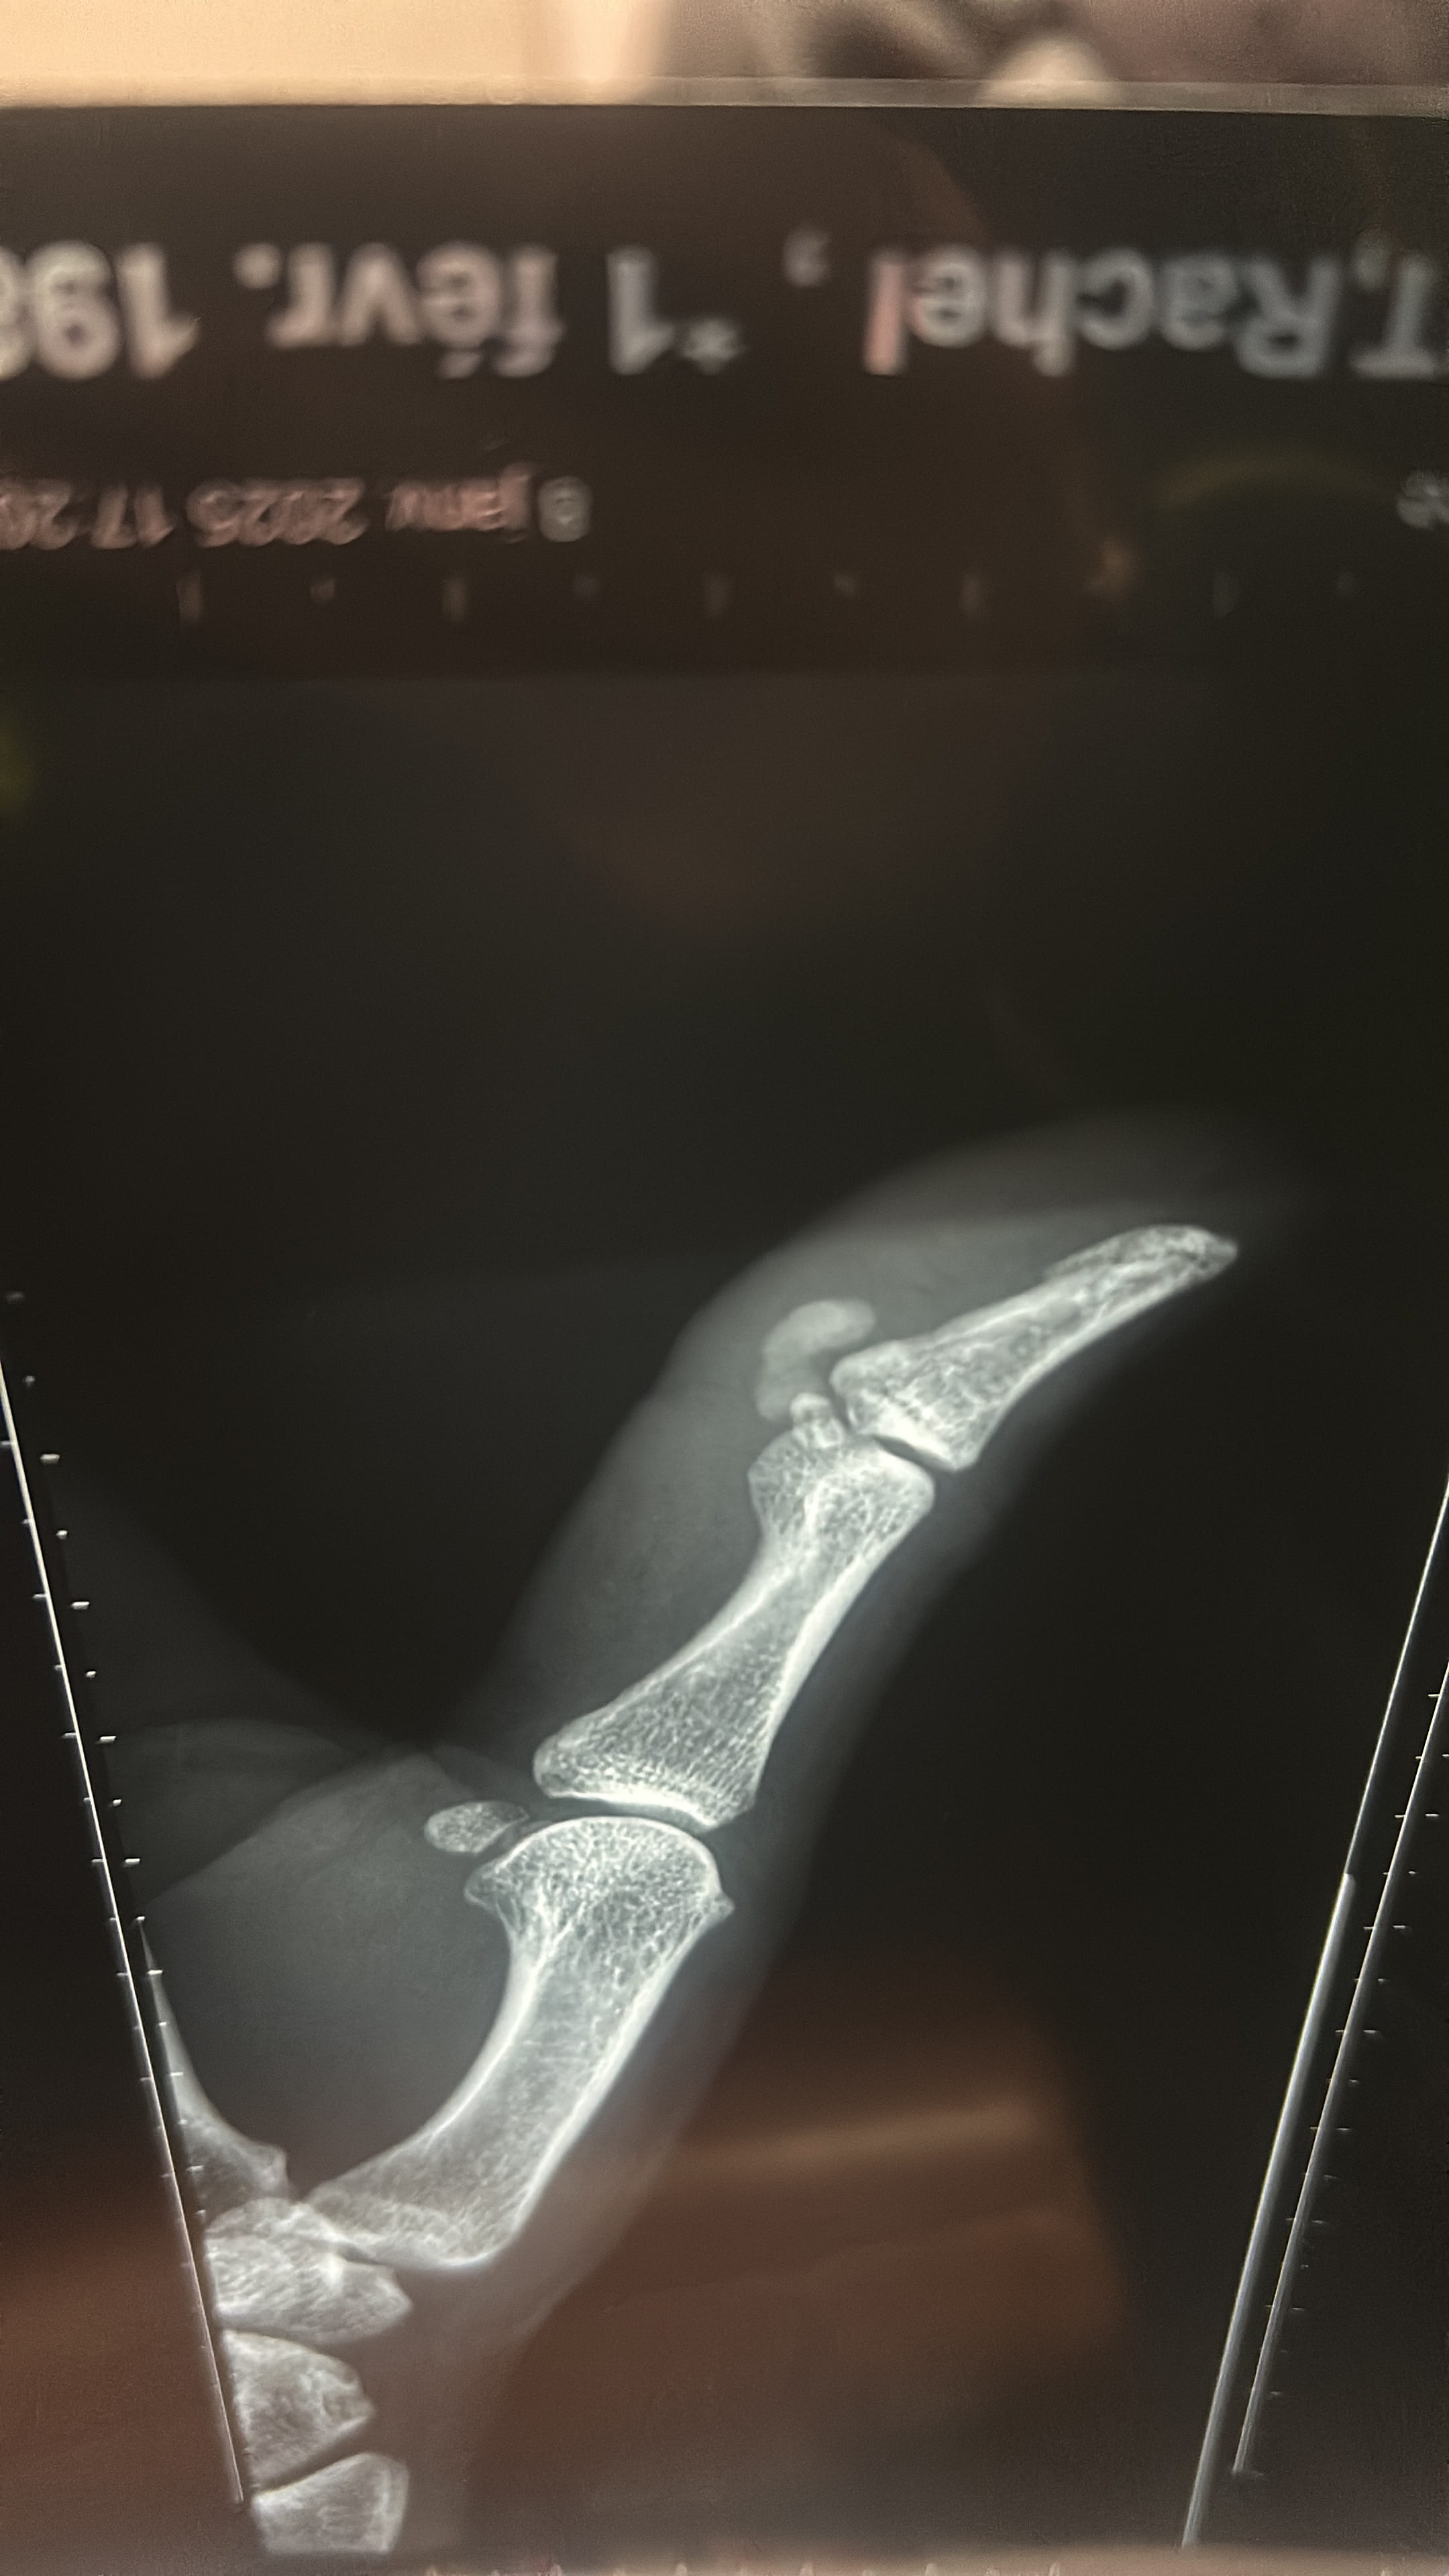

Cela fait 1 semaine que mon pouce est gonflé fois 3….

impossible de le mobiliser il est chaud et rouge !

radio faite ou l’on me dirige vers un chirurgien que je vois mardi car personne ne sait me dire ce que c’est ni mon généraliste ni le personnel urgentistes.

Sur le conte rendu ils parlent de masse?